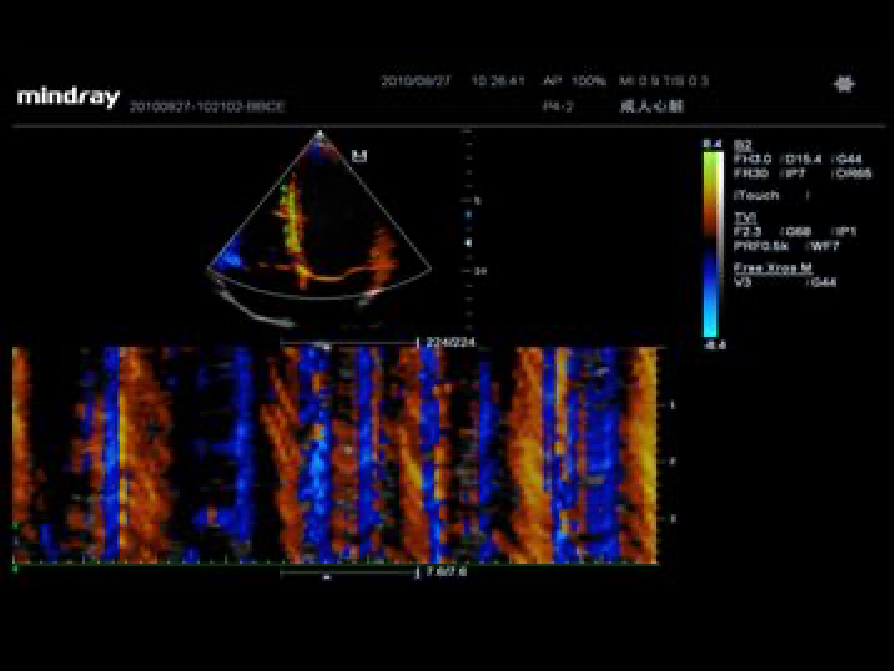

iBeamTM(Spatial Compound Imaging)

Permits use of multiple scanned angles to form a single image, resulting in enhanced contrast resolution and improved visualization.

Tissue Doppler Imaging allows you to quantitatively evaluate local myocardial movement and function, providing complete TDI modes for faster and direct diagnoses.